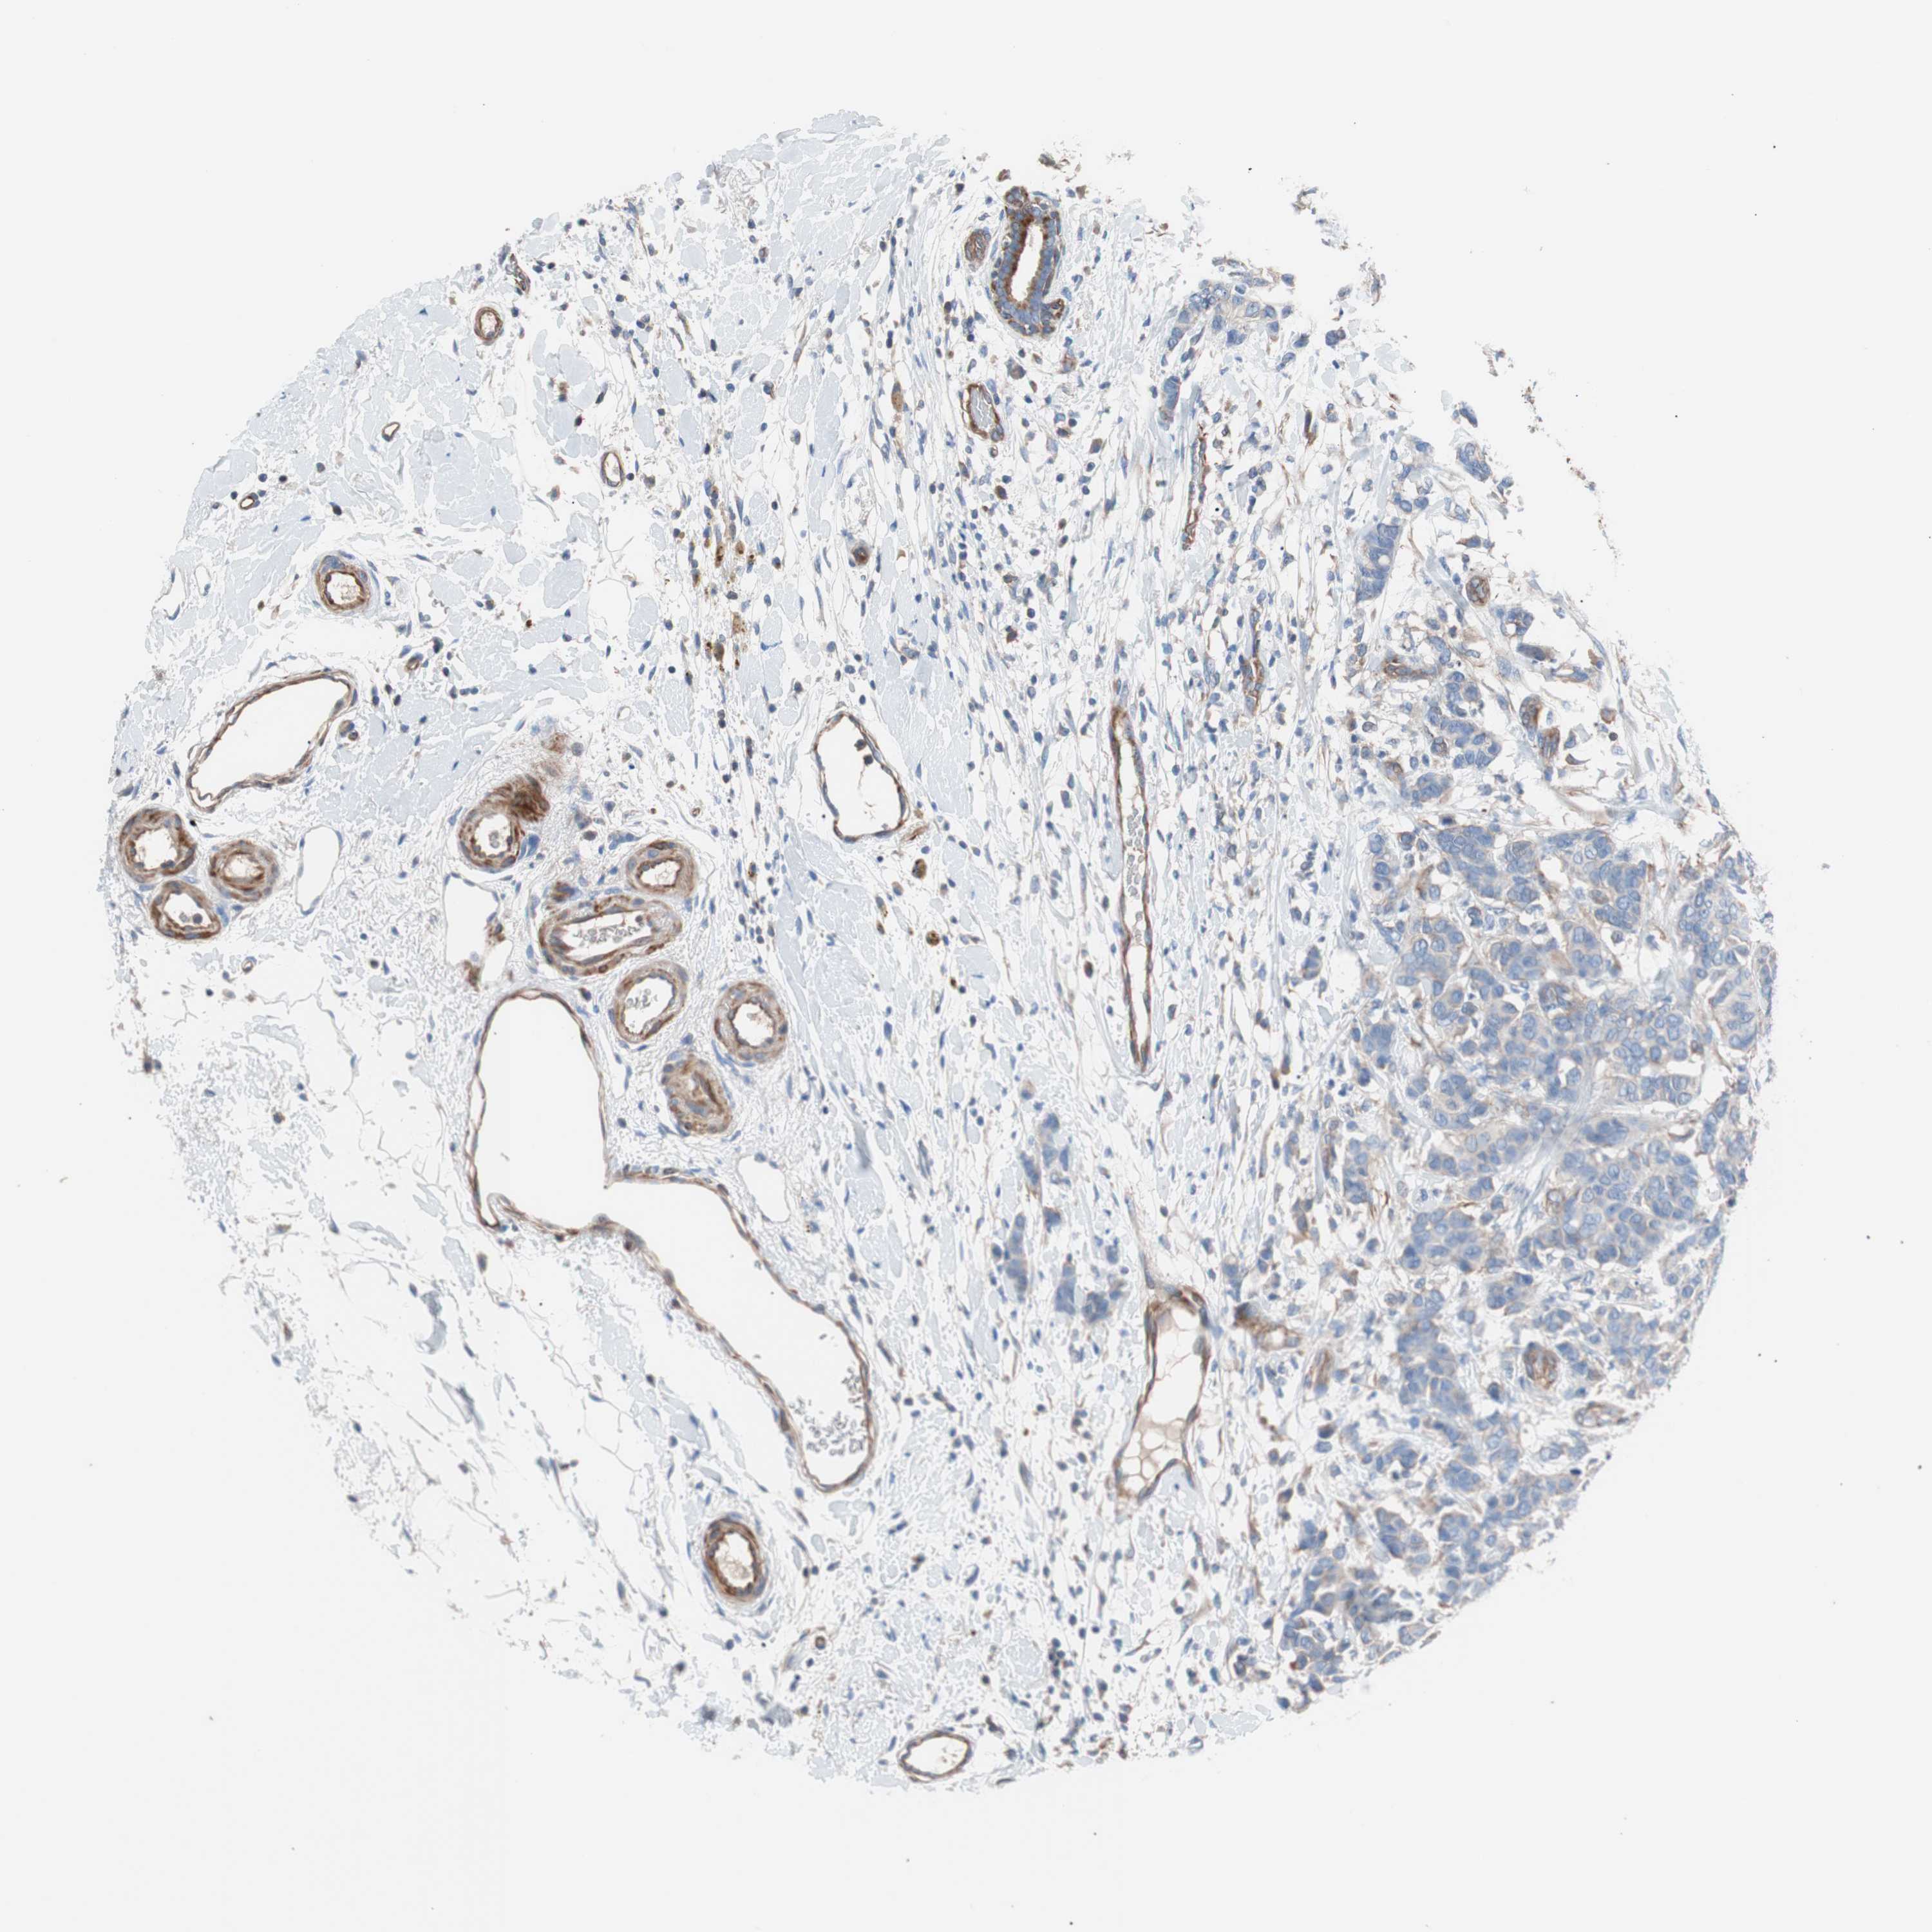

CANCER BREAST CANCER Show tissue menu

BRCA TCGA BRCA VALIDATION PROTEIN EXPRESSION